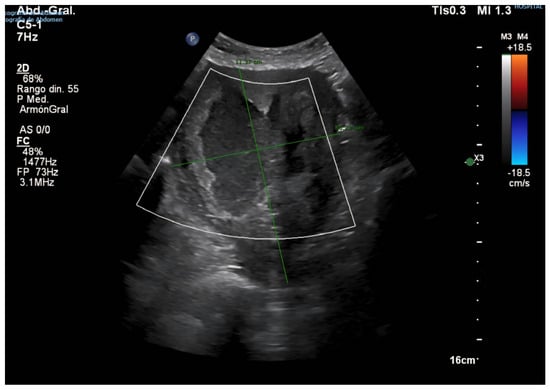

2. Case Presentation